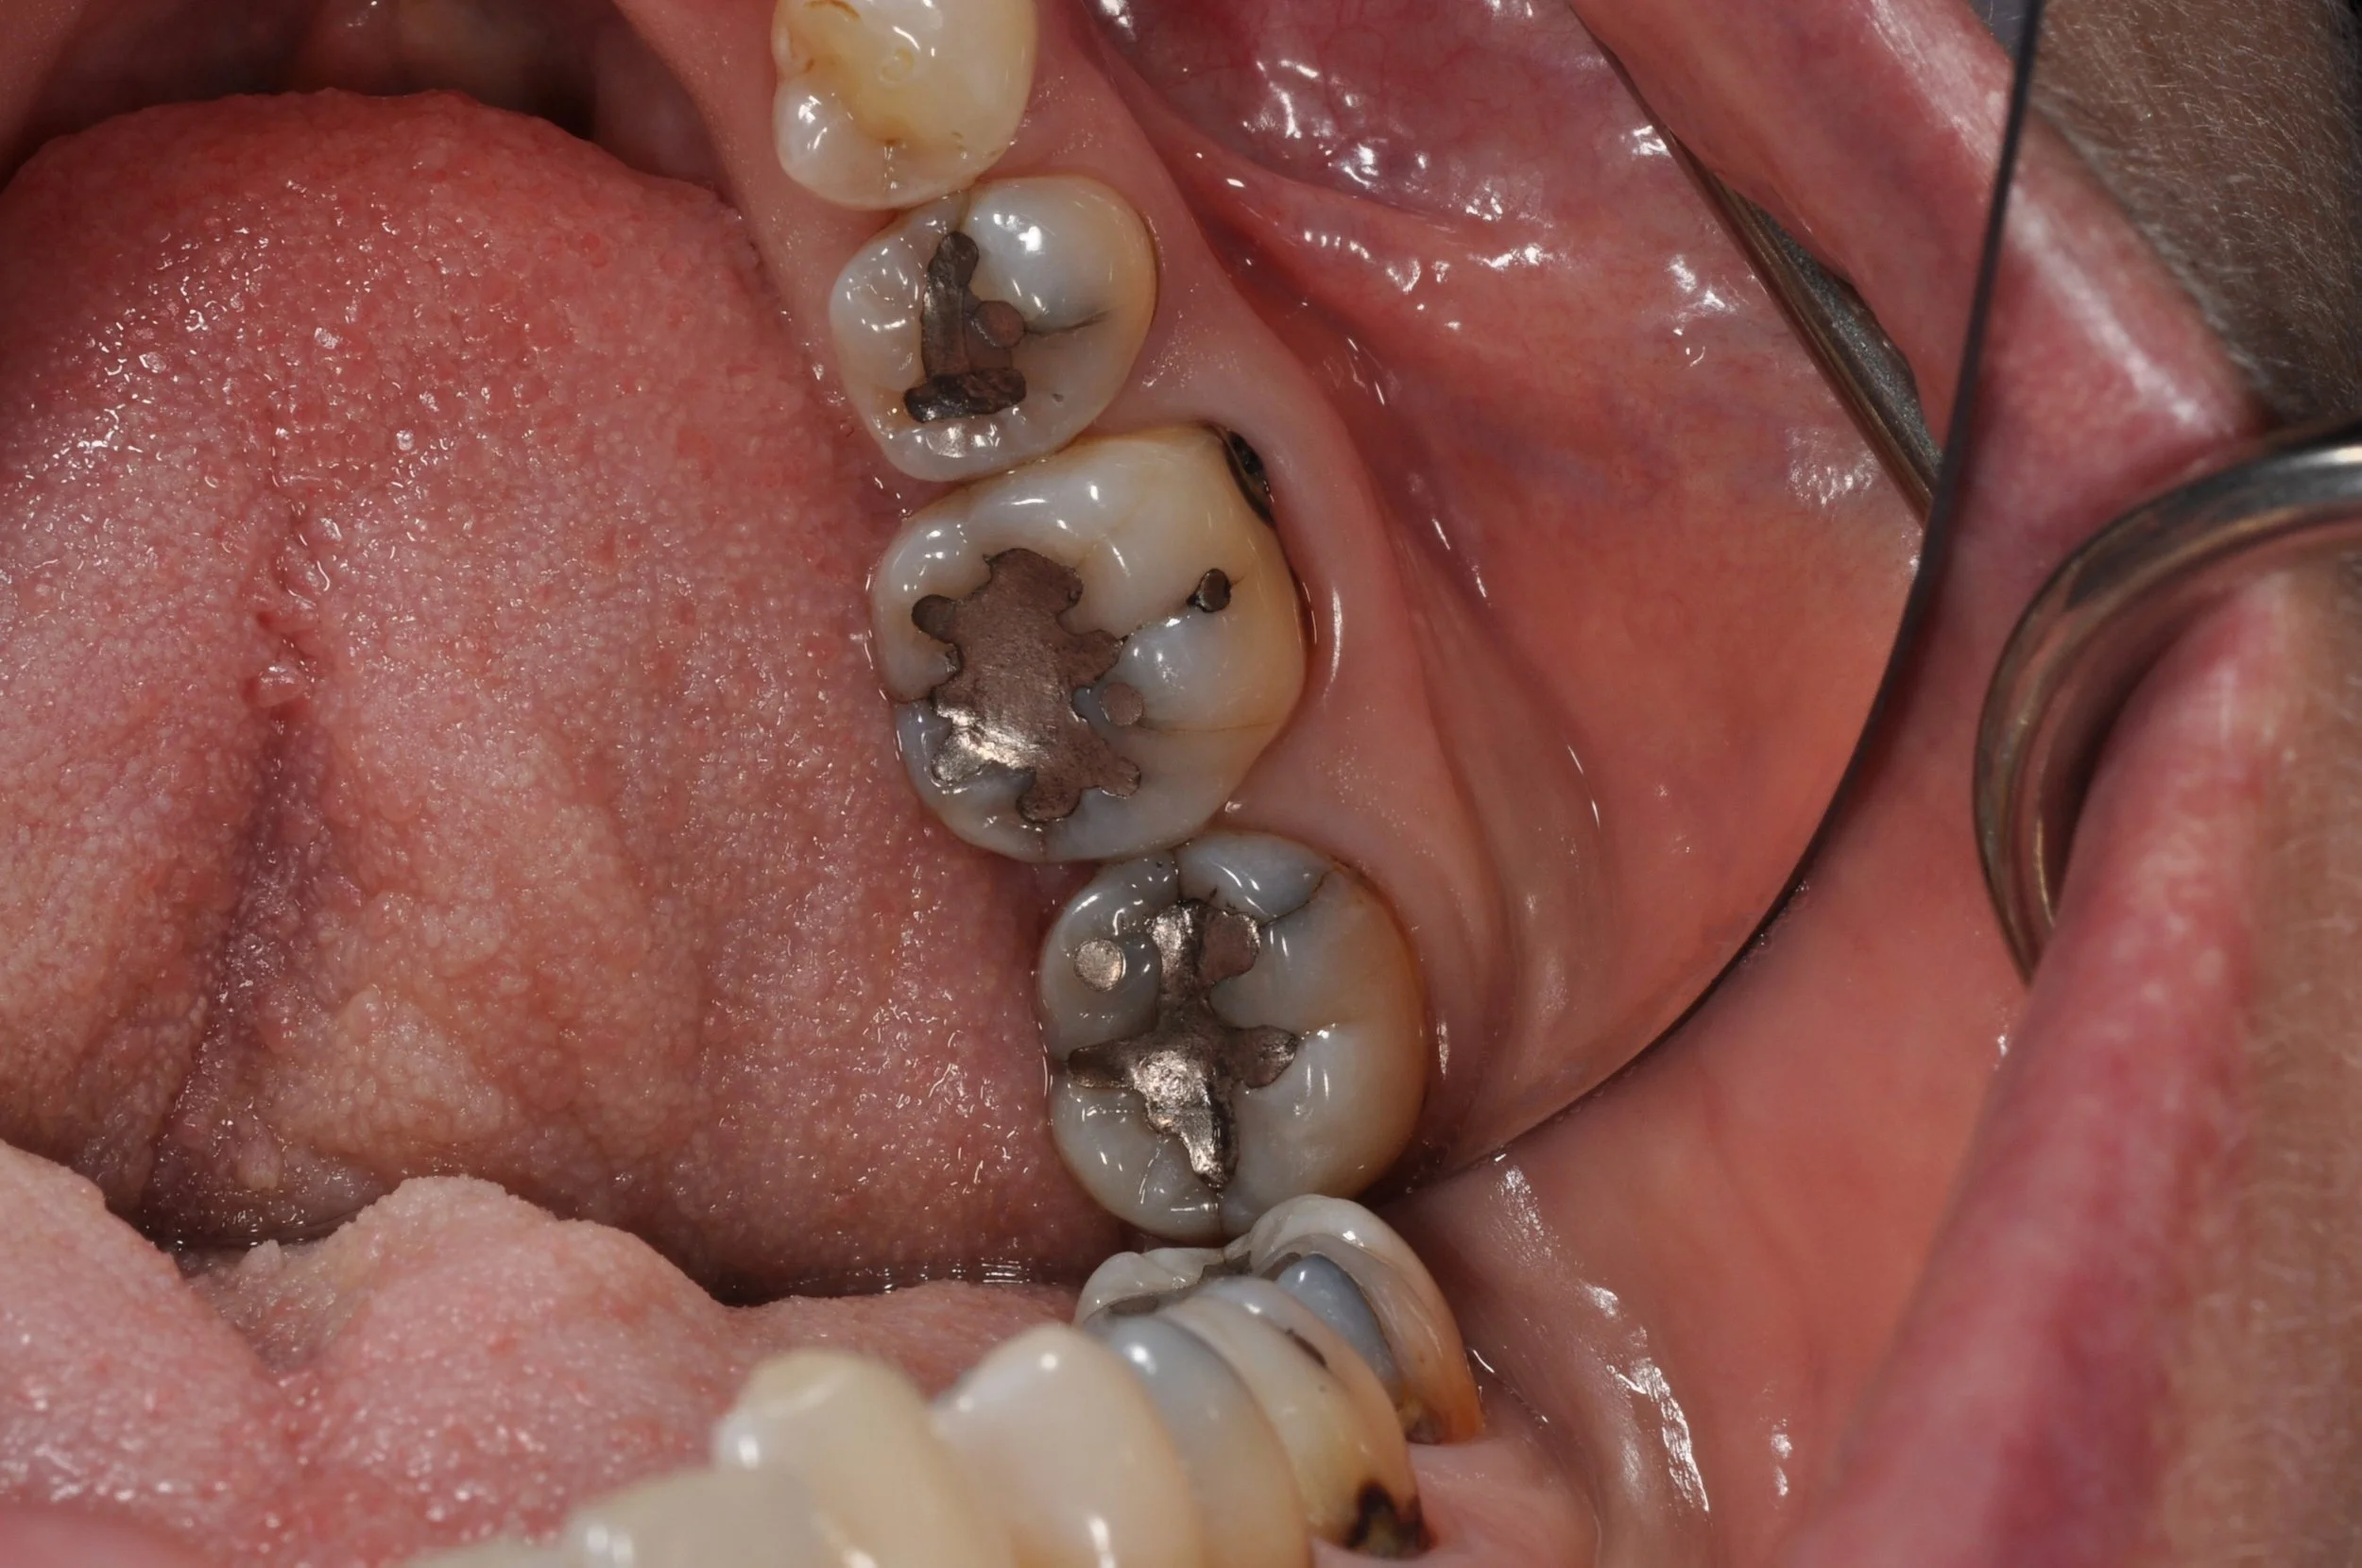

Close-up of a person's open mouth showing several molars with silver dental fillings.